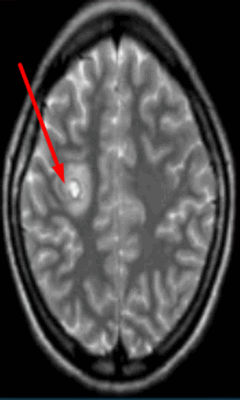

Очаг демиелинизации на МРТ

Очаги ишемии на МРТ

Очаги ишемии

Нарушения мозгового кровообращения приводят к кислородному голоданию тканей, что может спровоцировать их некроз (инфаркт). Ишемические очаги при Т2 взвешенных последовательностях выглядят как зоны с умеренно гиперинтенсивным сигналом неправильной формы. На более поздних сроках при проведении в Т2 ВИ или FLAIR режиме МРТ единичный очаг приобретает вид светлого пятна, что указывает на усугубление деструктивных процессов.